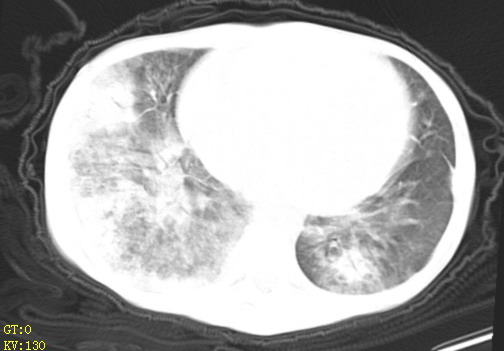

女,12岁,气促、咳嗽2天,3个月前查胸片示:两肺感染,急诊入院查ct,血常规等未检查。

左肺上叶改变考虑继发性肺结核,余双肺重症肺炎不排除h1n1。双侧胸腔少量积液。

1)考虑两肺感染性病变;建议抗炎治疗后复查。2)双侧少量胸腔积液。

双肺中下野不规则片絮状阴影,中外带明显,双侧胸腔少量积液,心影增大,心腔密度减低,隆突下及左侧气管旁见钙化淋巴结影,考虑双肺感染、心衰;建议结合临床除外h1n1并急性心衰,先心不能排除。

两肺多发片絮状模糊影,以下肺外带居多,内见支气管气像,纵膈窗未减影,两侧胸腔积液,心影增大,结合心超,支持重症肺炎,非常时期,甲型h1n1流感不排除。